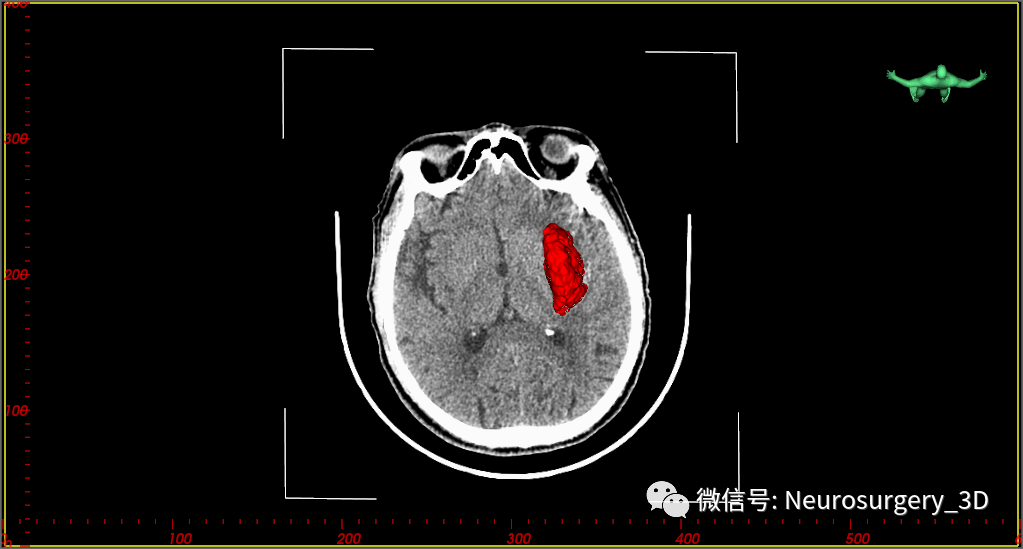

两天后的CT复查(2020年7月30日9:46)并测量不同区域的CT阈值,三维重建阈值选择45-100,包含低密度血肿区域。

我中心近年来多次遇到这种CT征象:1、血肿内存在界限分明的高密度区域和低密度区域,且低密度区域呈半包围于高密度区域;2、多次CT复查,高密度血肿增加不明显,血肿扩大为低密度血肿;3、一般初次CT检查是高密度血肿,2-3天后血肿体积扩大,扩大的血肿为低密度血肿,高密度血肿无扩大。其形成机制考虑为长期饮酒或口服抗凝药物后,脑部小血管破裂出血致血肿凝固析出渗液,低密度血肿所含血清成分较多,为不凝液状态。这种形态血肿微创穿刺治疗血管比较理想,手术也证实,在微创手术中液态部分能较容易引出,起到迅速减压,缓解颅内压力的目的。

两种治疗方案截然不同,只有精准判断出出血类型,恰当选择治疗方法,术后效果立现。该病例我们首选微创钻孔置管引流术,为了把引流管精准的置入到低密度液态血肿部分,我们设计引流管顺血肿长轴进行,并把靶点置入到血肿中后1/3处,先引流液态血肿减压,再应用尿激酶液化高密度血肿部分。